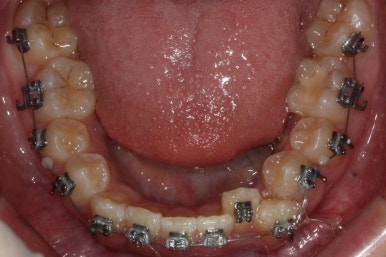

이제 치료가 끝났습니다.

매우 치아가 가지런해졌고, 당연히 덧니는 해소가 되었으며 맞물림도 굉장히 좋아졌습니다.

다른 분드로가의 차이점은 치료 종료 후 유지장치를 할 때 앞니만 하는 것이 아니라 발치한 자리가 다시 벌어지지 말라고 약간 연장해서 유지장치를 부착해 주게 됩니다.